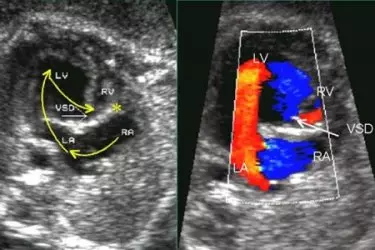

During the second trimester around 14-15 weeks of pregnancy a very detailed and indepth ultrasound is done called Level II Scan which gives complete information about the congenital abnormalities in the foetus. Not every radiologist is good at doing the Level 2 Scan and this is where highly experienced sonologists like Dr Singh come into the picture.